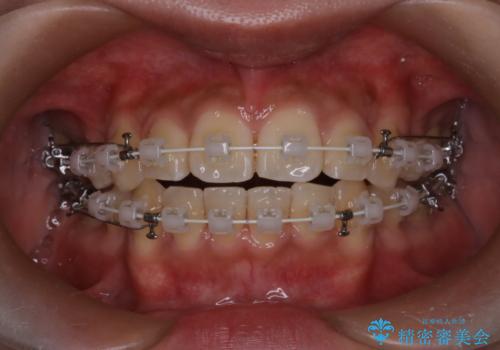

- 前歯の突出が強く、口元が前に出ている印象を改善するため、上下左右の第一小臼歯(4番)を抜歯する矯正治療を計画しました。抜歯により得られたスペースを利用して、前歯を後方へと移動させて整列します。治療には目立ちにくい透明な審美ブラケットとワイヤーを使用し、毎月1回の調整を行いながら徐々に歯を動かし、約2年で口元全体を整える計画としました。

前歯が前に出ているため口元が突出し、唇が閉じにくいなどの悩みを抱えておられました。治療にあたり上下左右の第一小臼歯を抜歯し、十分なスペースを作ることで前歯を効果的に後方へ移動させました。装置には透明で目立ちにくい審美ブラケットを採用し、治療中の審美的ストレスを軽減しました。定期的な調整を通じて無理なく確実に歯列を整え、前歯の突出感を解消。治療後は口元の印象が自然で美しく改善され、患者様には非常にご満足いただけました。